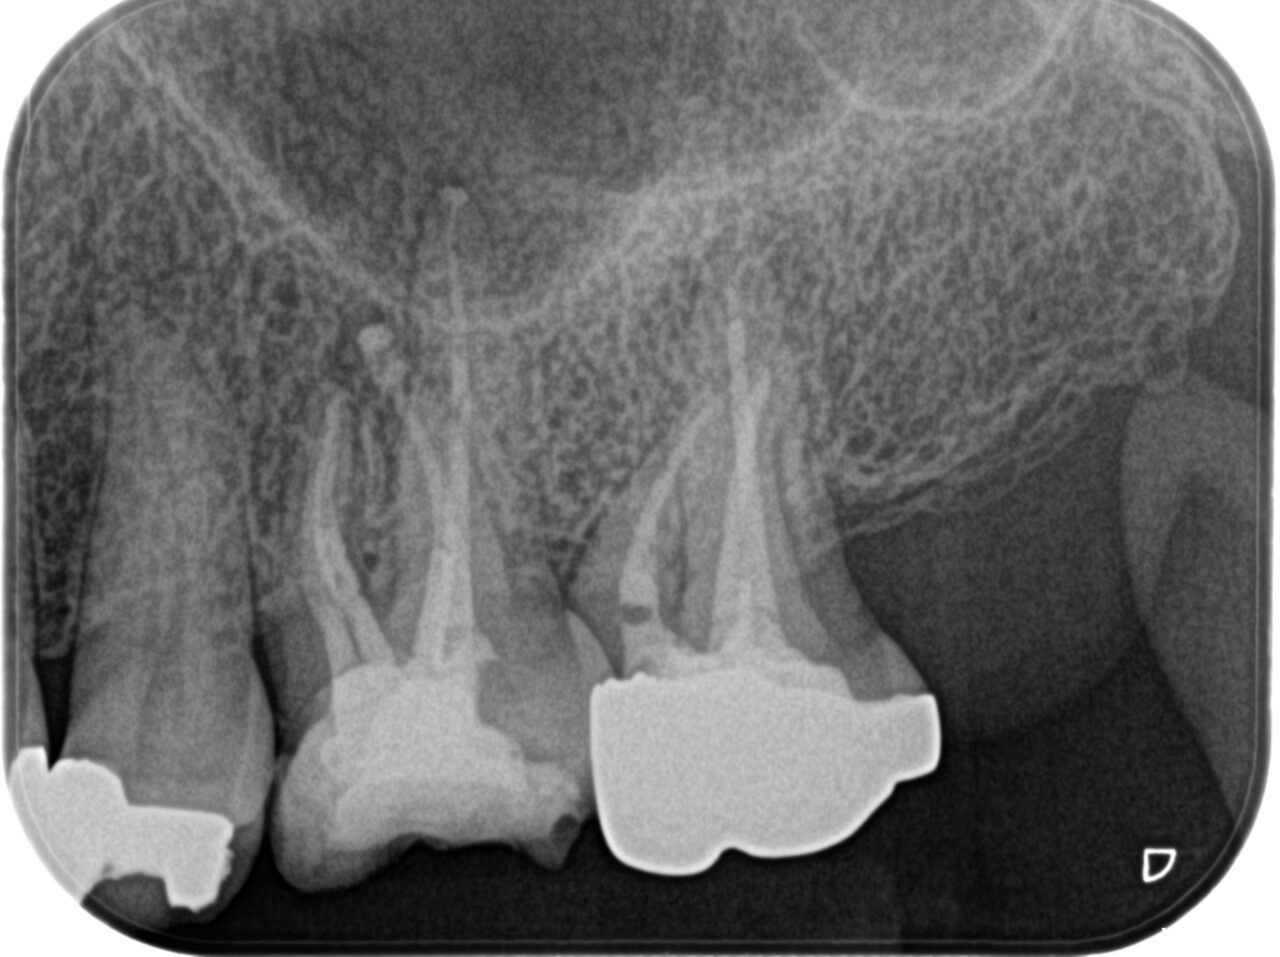

症例1

Before

After

年齢/性別 | 40代/女性 |

|---|---|

主訴 | 根の先の膿を治してほしい マイクロスコープを使用して根管治療をしてほしい |

治療内容 | ラバーダム防湿、マイクロスコープを使用した精密な根管治療 |

治療回数 | 根管治療1回で完了 |

治療費 | 根管治療+被せ物 約25万円 |

注意点 | この根管には偽根管と本来の根管とは違う、人為的な偽の根管が存在。本来の根管の中の感染源を除去するのが困難な症例。ニッケルチタンファイルを使用しプレカーブを付与して本来の根管へアプローチした。近心根管にMB2がCTで確認できた。しかし、非常に狭窄している。通常の器具では未治療根管となるだろう。 |